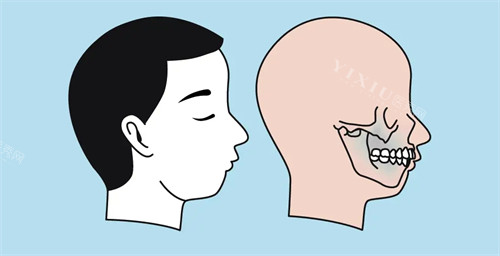

一、什么是骨性嘴凸?

骨性嘴凸主要表现为上颌前突或下颌后缩,导致嘴唇无法自然闭合。与单纯牙齿不齐不同,这种问题涉及颌骨发育异常,需要早期干预才能取得理想结果。